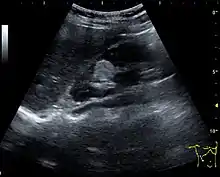

One of the primary indications for referral to US evaluation of the kidneys is evaluation of the urinary collecting system. Enlargement of the urinary collecting system is usually related to urinary obstruction and can include the pelvis, the calyces and the ureter. Hydronephrosis is seen as an anechoic fluid-filled interconnected space with enhancement within the renal sinus, and normally, the dilated pelvis can be differentiated from the dilated calyces.[1]

Several conditions can result in urinary obstruction. In both adults and children, masses, such as abscesses and tumors, can compress the ureter. In children, hydronephrosis can be caused by ureteropelvic junction obstruction, ectopic inserted ureter, primary megaureter and posterior urethral valve (Figure 13). In the latter, both kidneys will be affected. In adults, hydronephrosis can be caused by urolithiasis, obstructing the outlet of the renal pelvis or the ureter, and compression of the ureter from, e.g., pregnancy and retroperitoneal fibrosis. Urolithiasis is the most common cause of hydronephrosis in the adult patient and has a prevalence of 10%–15%.[1]